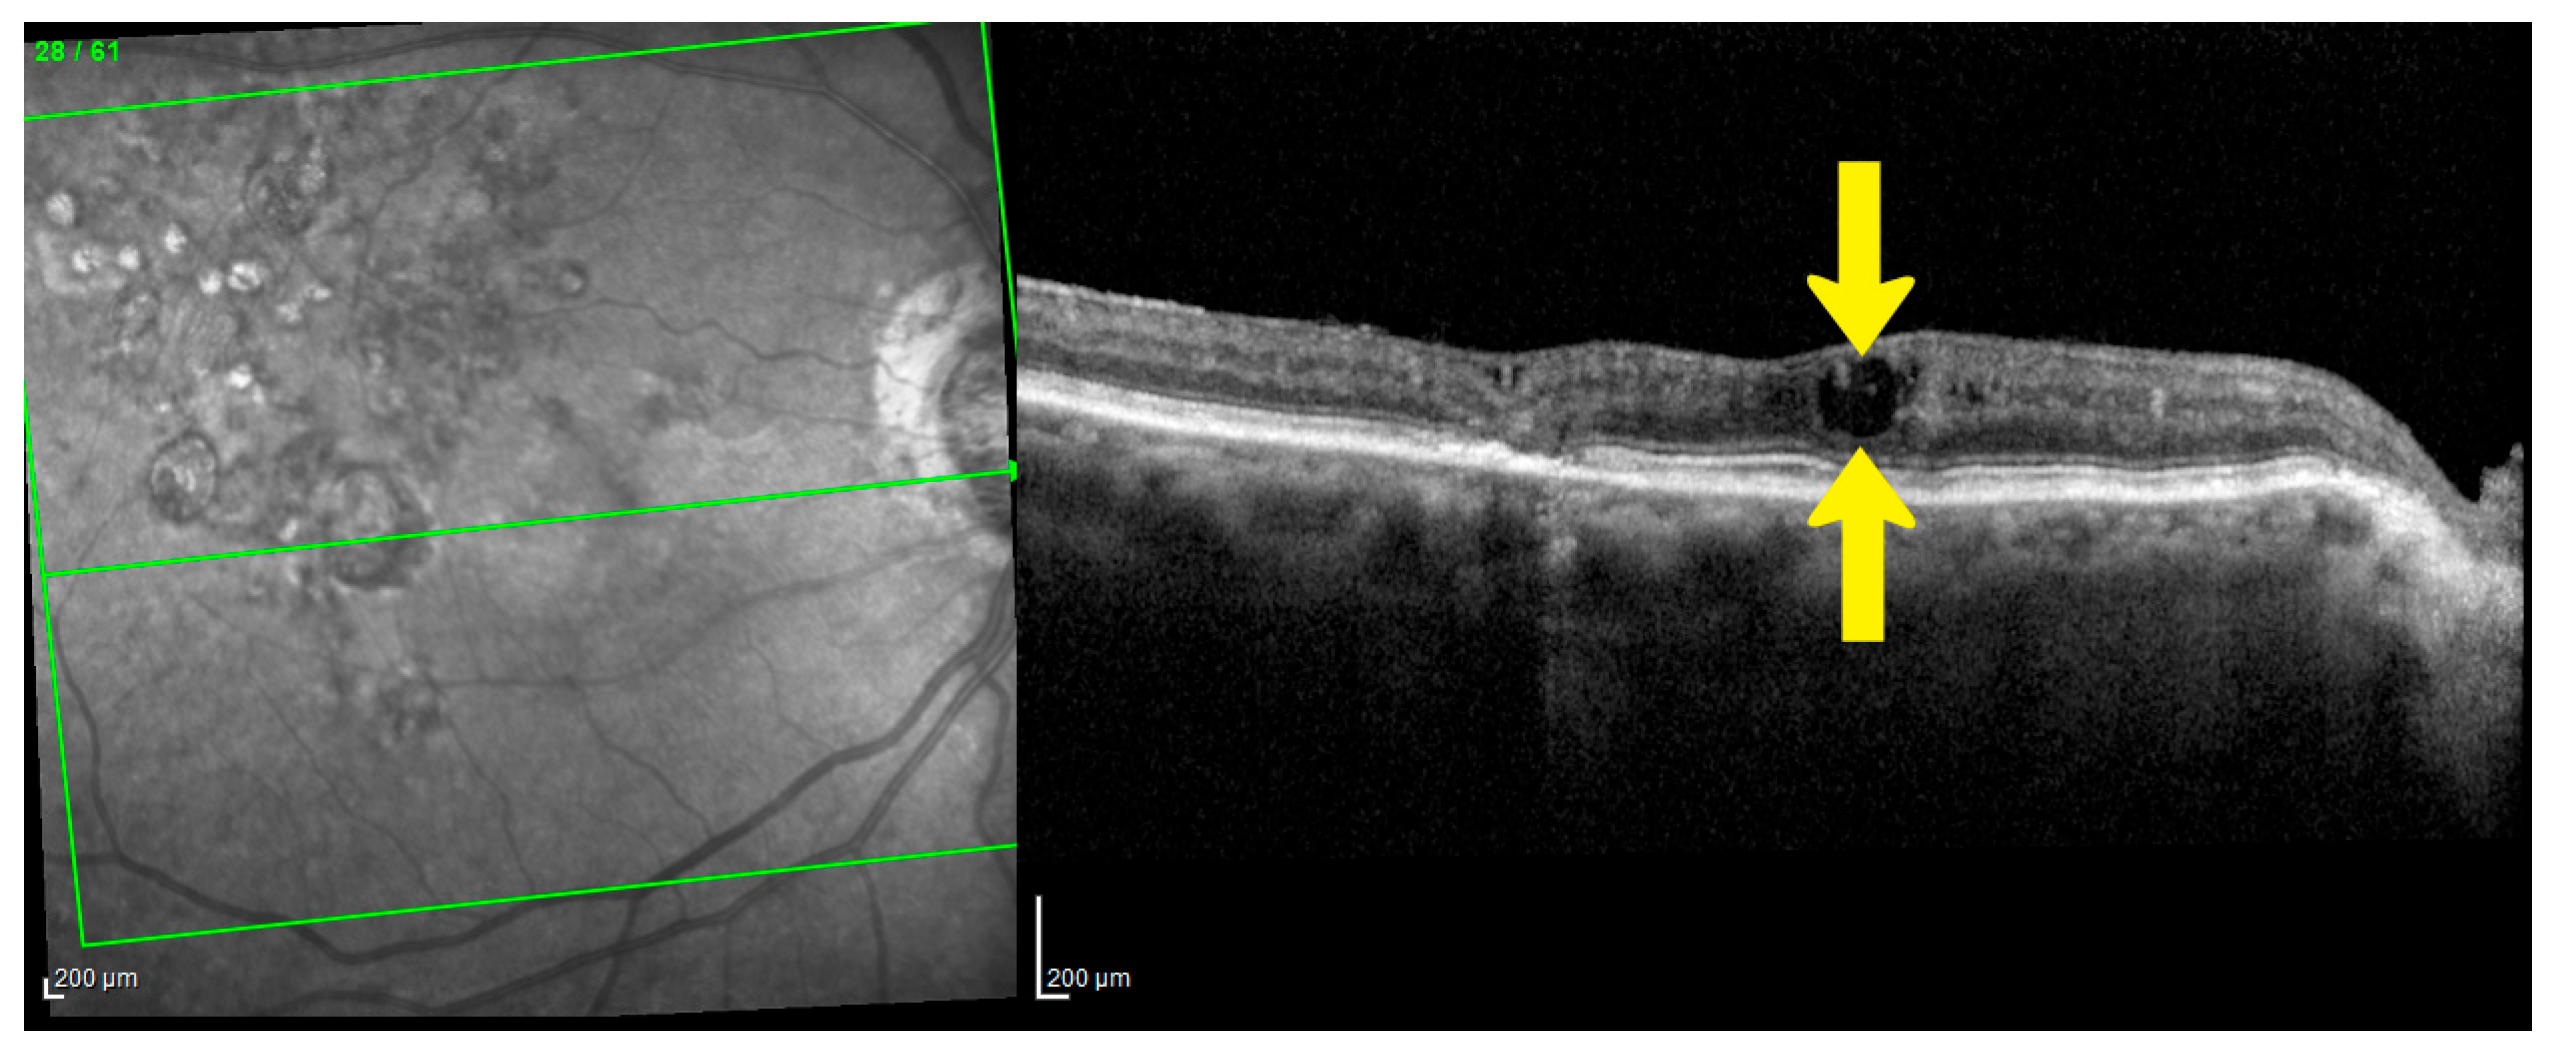

- Otani, T.; Kishi, S.; Maruyama, Y. Patterns of diabetic macular edema with optical coherence tomography. Am. J. Ophthalmol. 1999, 127, 688–693. [Google Scholar] [CrossRef] [PubMed]

- Spaide, R.F. Retinal Vascular Cystoid Macular Edema: Review and New Theory. Retina 2016, 36, 1823–1842. [Google Scholar] [CrossRef] [PubMed]

- Yanoff, M.; Fine, B.S.; Brucker, A.J.; Eagle, R.C. Pathology of human cystoid macular edema. Surv. Ophthalmol. 1984, 28 (Suppl. 2), 505–511. [Google Scholar] [CrossRef] [PubMed]

- Deák, G.G.; Bolz, M.; Ritter, M.; Prager, S.; Benesch, T.; Schmidt-Erfurth, U. A Systematic Correlation between Morphology and Functional Alterations in Diabetic Macular Edema. Investig. Ophthalmol. Vis. Sci. 2010, 51, 6710–6714. [Google Scholar] [CrossRef]

- Yalçın, N.G.; Özdek, Ş. The Relationship Between Macular Cyst Formation and Ischemia in Diabetic Macular Edema. Turk. J. Ophthalmol. 2019, 49, 194. [Google Scholar] [CrossRef]

- Murakami, T.; Nishijima, K.; Akagi, T.; Uji, A.; Horii, T.; Ueda-Arakawa, N.; Muraoka, Y.; Yoshimura, N. Optical Coherence Tomographic Reflectivity of Photoreceptors beneath Cystoid Spaces in Diabetic Macular Edema. Investig. Ophthalmol. Vis. Sci. 2012, 53, 1506–1511. [Google Scholar] [CrossRef]